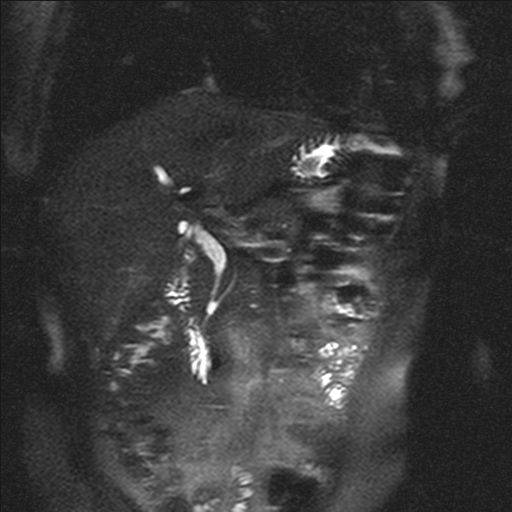

门诊MRCP :胰管与胆总管交界处小囊样扩张,约0.5X0.6厘米,先天变异可能。胆囊管残端较长。肝内外胆管及胰管未见明显扩张。